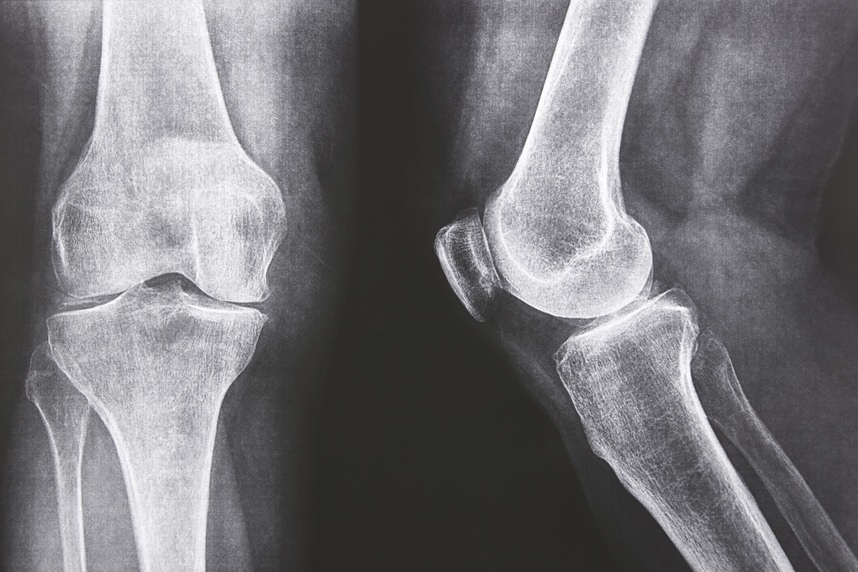

Rheumatology specialists diagnose and treat:- Degenerative conditions – cervical or lumbar spondylosis, disc herniation, knee osteoarthritis, hip osteoarthritis, osteoarthritis of the hands or shoulders;

- Autoimmune conditions – rheumatoid arthritis, ankylosing spondylitis, systemic lupus erythematosus, scleroderma;